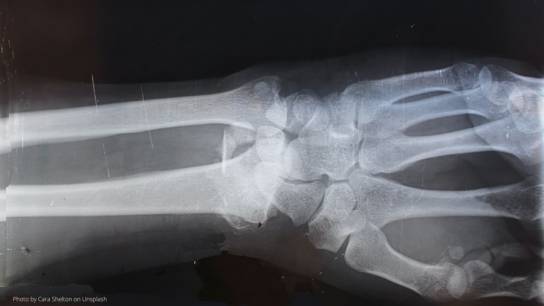

The complex and multifaceted disease group of RMDs is one of the leading causes of disability worldwide. RMDs include more than 200 different conditions such as rheumatoid arthritis, osteoarthritis, gout as well as lupus. All of these diseases can affect people of all ages – both physically and emotionally.

Rheumatoid arthritis is one of seven diseases in the focus of the 3TR project. The 3TR research teams will analyse and compare this disease alongside and together with six other immune-mediated diseases with the ultimate aim to improve treatment responses.